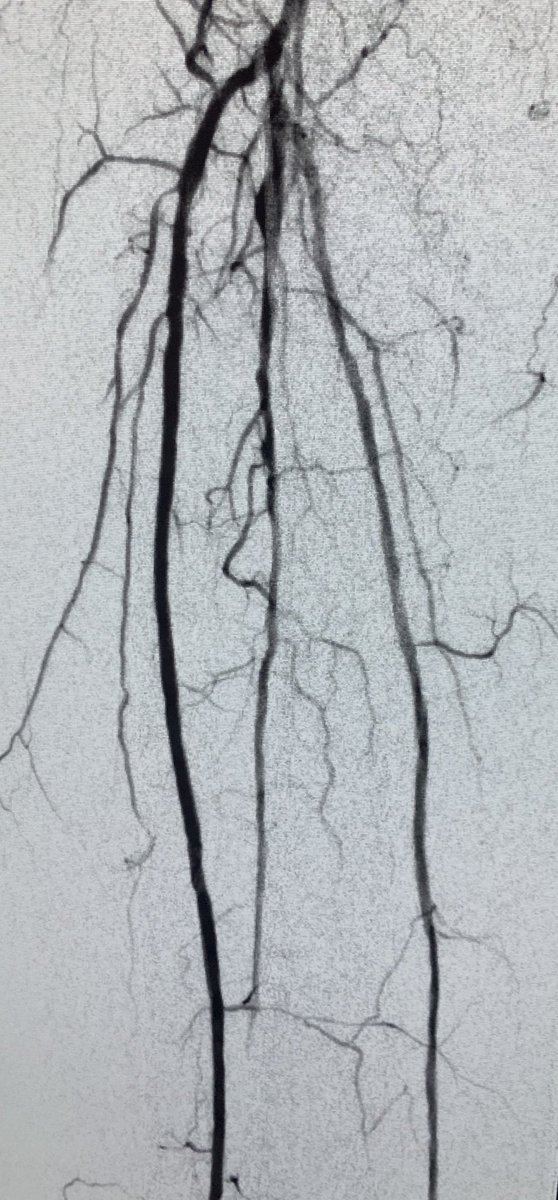

MRA can be MORE sensitive to tibial occlusive disease than DSA. MRA helped plan approach due to knowledge of hibernating AT and peroneal lumen. Successful antegrade luminal recan for #CLI #CLIfighters #mylegmylife @FadiSaab17 @Mustapja @roblookstein @DrBTKatzen @BOlivieriMD